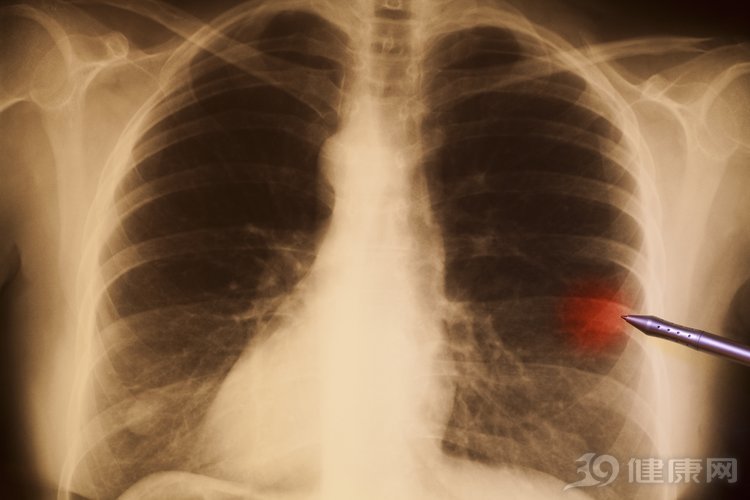

肺癌是一种发病率很高的癌症,而且也是一种死亡率非常高的癌症,事实上,癌症的发病都是有前兆的,肺癌也不例外,比如出现杵状指就可能是肺癌发出的警报。国内外有很多报道都表示,出现杵状指的人有八成都是肺癌导致的。

广州医科大学附属第二医院的呼吸科主任陈飞鹏就提出过:杵状指产生的原因多数是由于心肺疾病导致的,其中肺部疾病引起的杵状指患者占到了百分之七十五到八十,而心血管疾病患者出现杵状指的概率则占到百分之十到百分之十五,只要出现杵状指,背后肯定是有原因的,而且基本上导致杵状指出现的肿瘤一般都是恶性的。